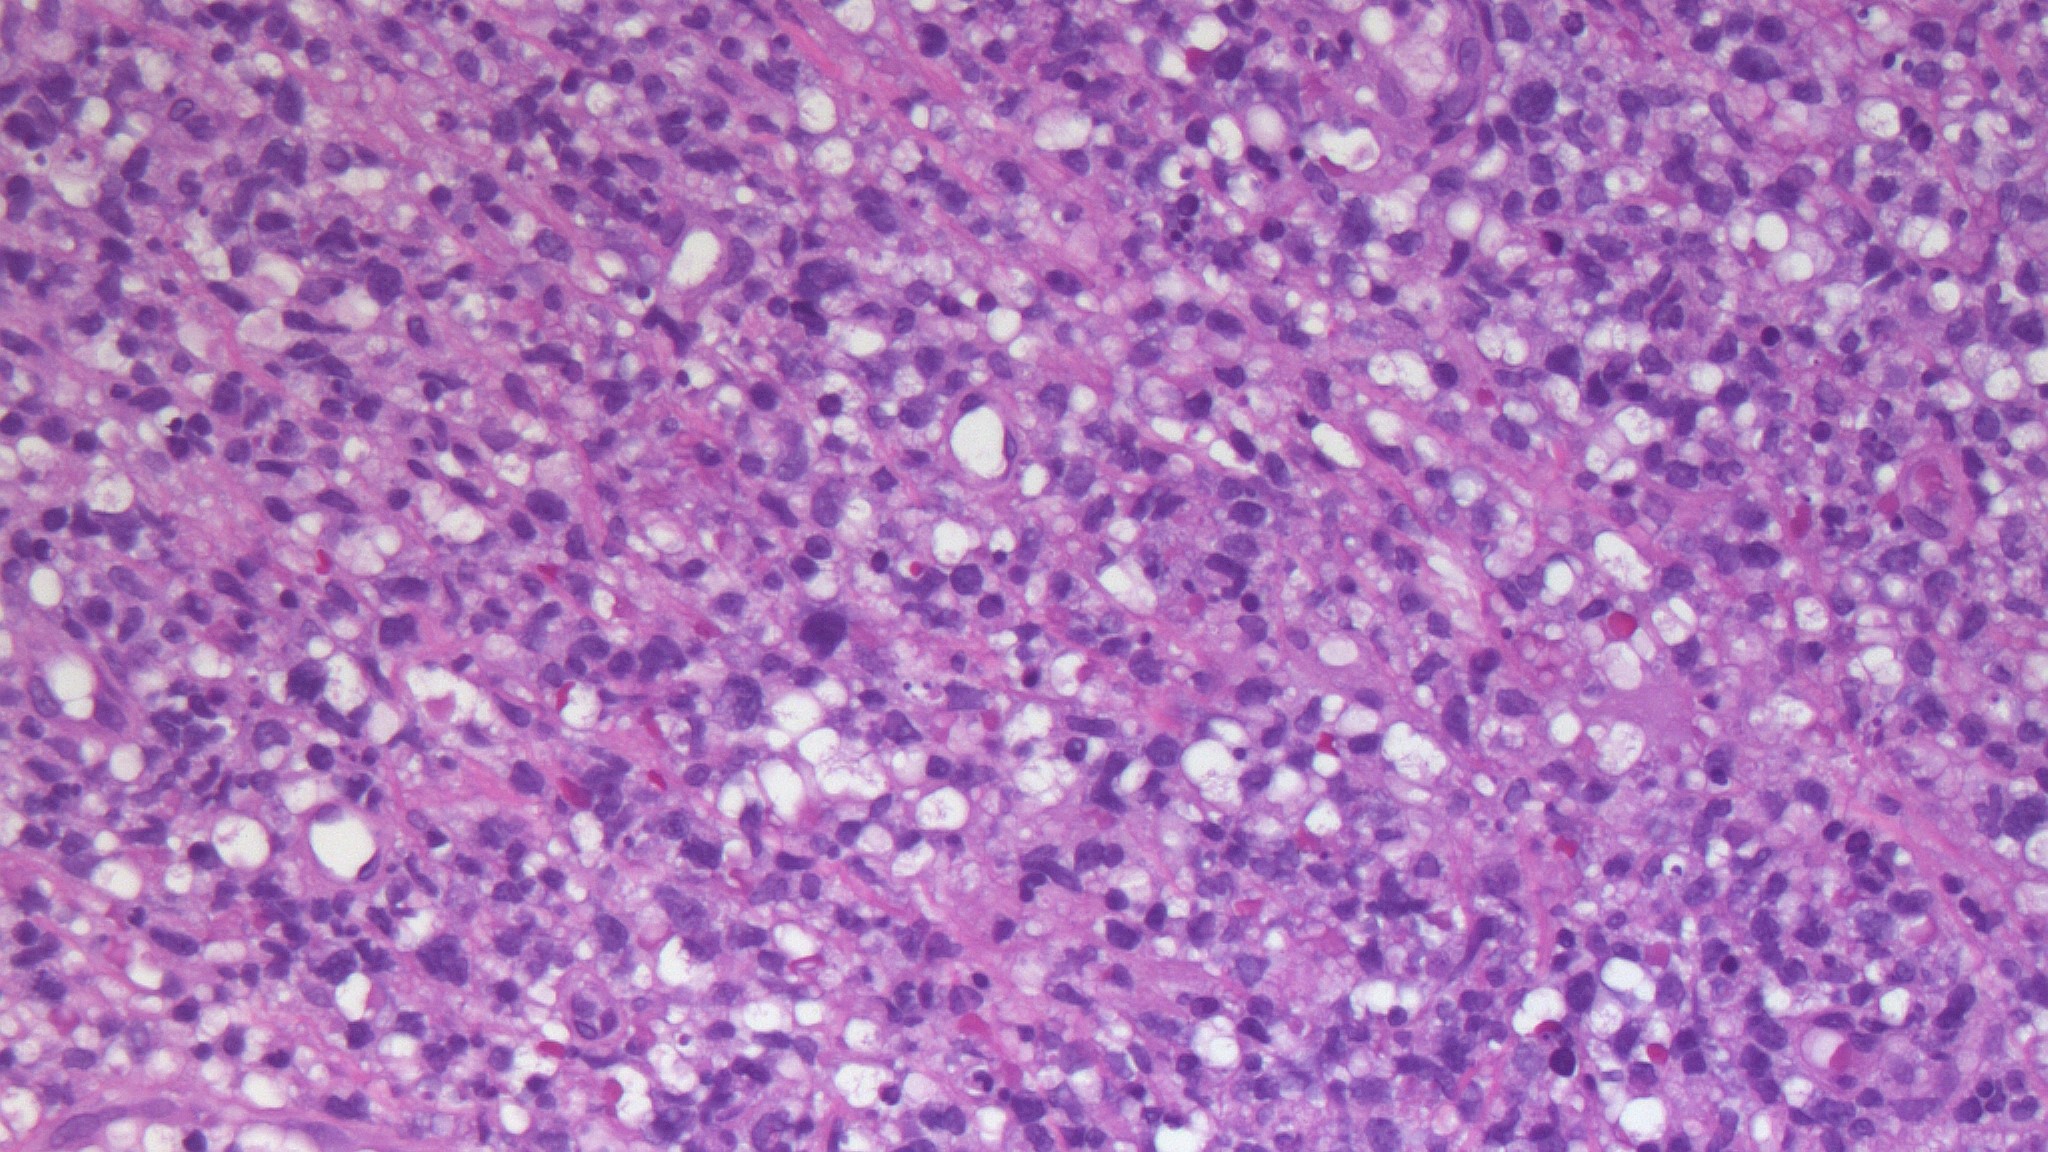

Диагностика лимфомы Ходжкина с помощью ПЭТ и КТ